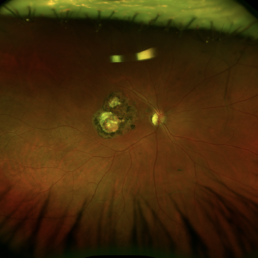

Toxoplasmosis Macular Scar

Mar 8 2024 by Andre Beckenkamp

Optos image of a patient with extensive choriorretinal scar due to toxoplasmosis infection.

Photographer: Andre Beckenkamp,MD , Prevent Senior

Condition/keywords: toxoplasmosis